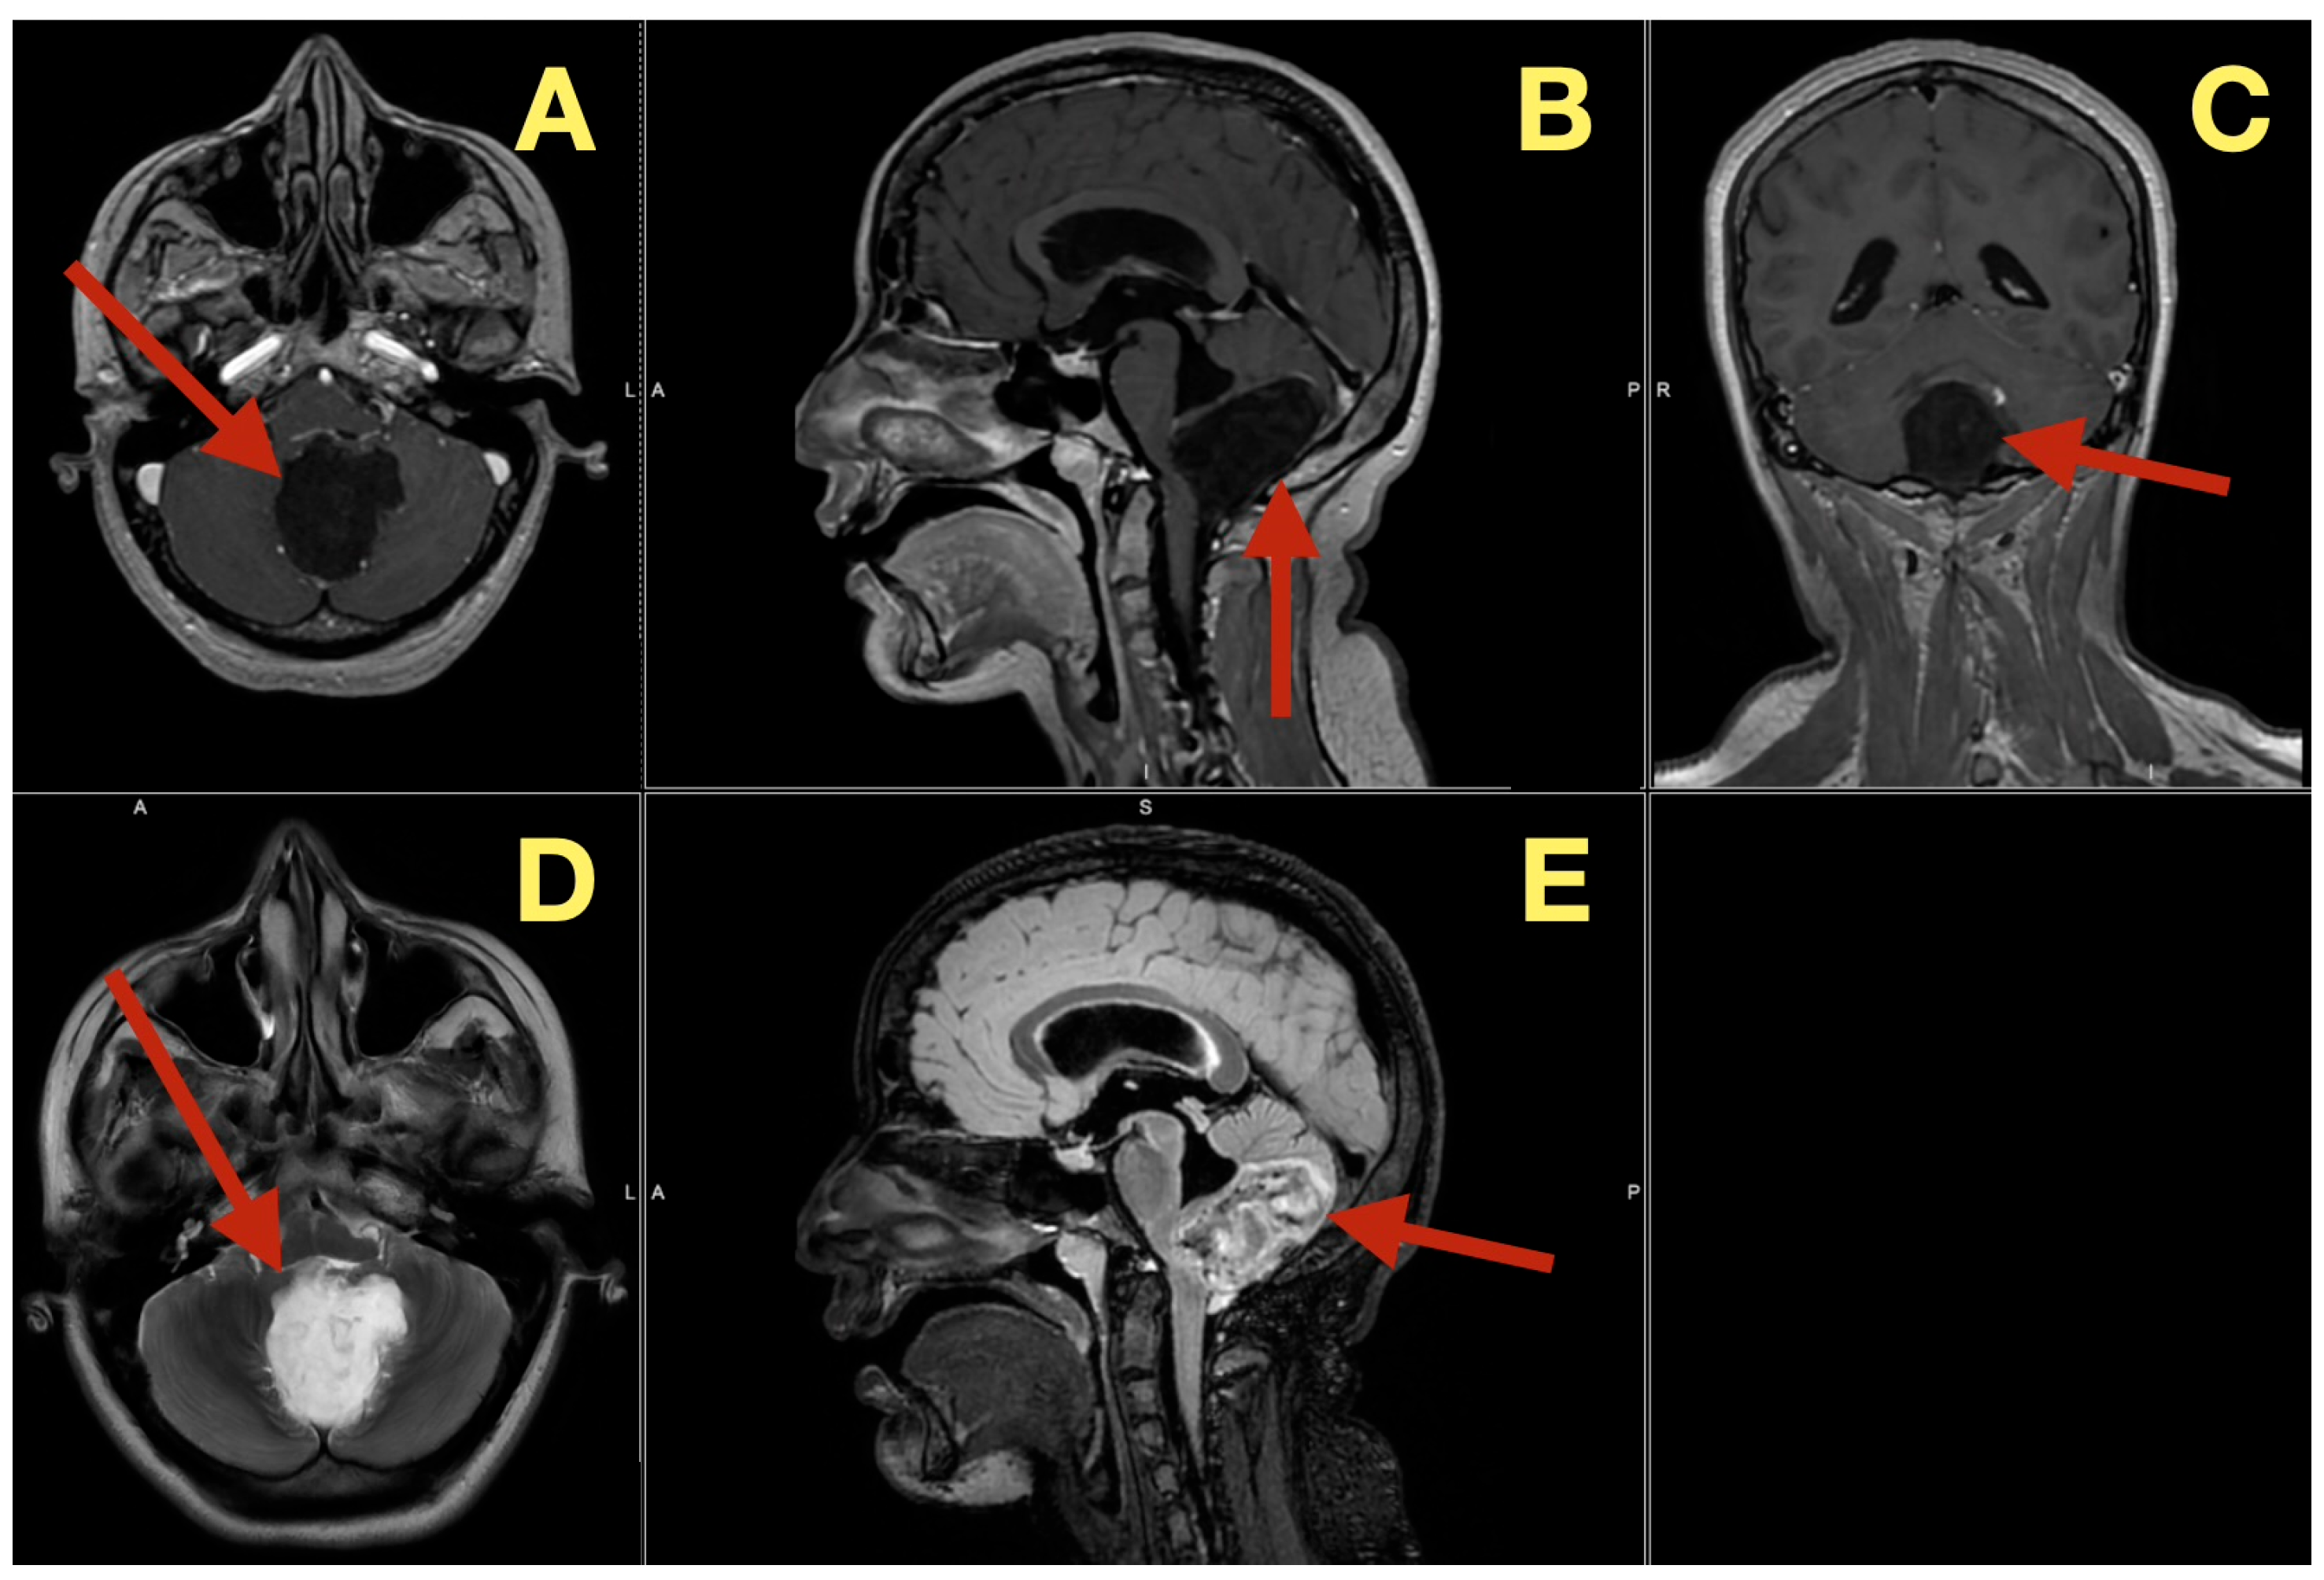

MRI scans five months after surgery (Figure 7), demonstrated that the post-operative cavity contained fluid with no enhancement and normal perfusion of the surrounding parenchyma, with no glial scar on FLAIR and no diffusion restriction on DWI, effectively ruling out remaining keratinous material.

Figure 7. Five-month postoperative MRI. (A): Axial T1-weighted image demonstrating a CSF-filled postoperative cavity with smooth margins and no enhancing tissue (arrow). (B): Sagittal T1 image showing sustained patency of the fourth ventricle and normal vermian convexity (arrow). (C): Axial perfusion map revealing normal parenchymal hemodynamics in the cerebellum surrounding the resection site (arrow). (D): Axial diffusion-weighted image showing absence of restricted diffusion, excluding residual keratinaceous material (arrow). (E): Sagittal FLAIR sequence illustrating clean CSF spaces and absence of gliosis (arrow). (F): Coronal T1 image confirming midline symmetry and complete restitution of cerebellar and brainstem anatomy (arrow).